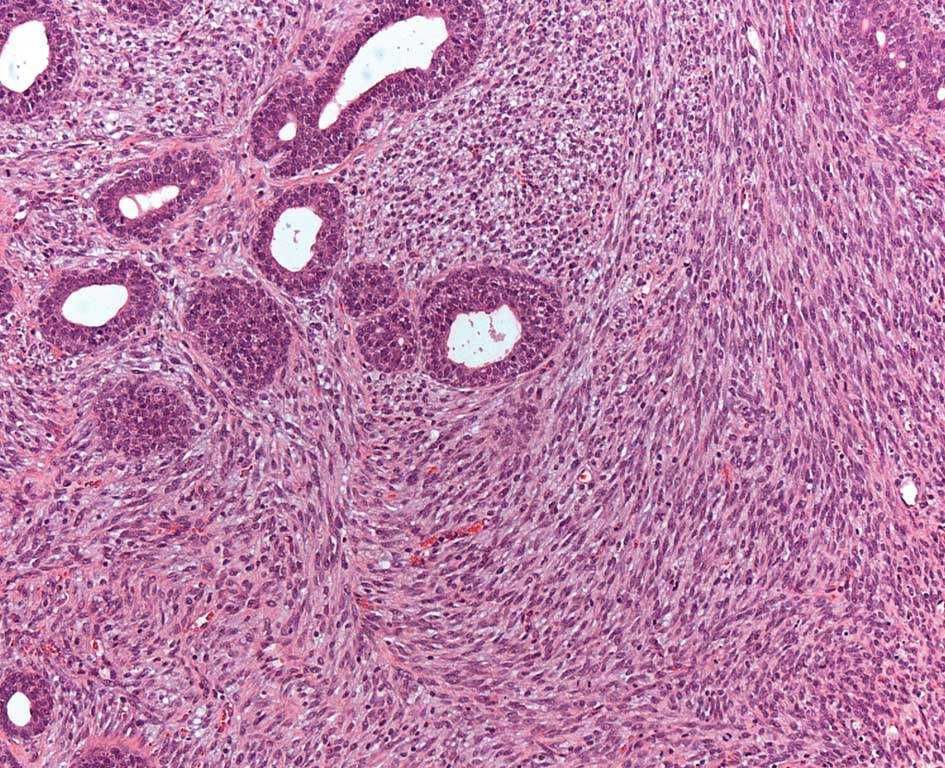

Mammary tumor histology data are presented in Table III. A total of 82 mammary tumors were detected in the study. Table III shows the light microscopic classification of these mammary tumors in the four groups. A total of 30 masses were detected (37% of the total tumors) in the lean casein-fed group compared to 18 tumors (21%) in the lean soy protein-fed group, 31 tumors (38%) in the obese soy protein-fed rats and only 3 tumors (4%) in the obese casein-fed rats. Pathological analysis of the 30 tumors in the lean casein-fed group showed the following classification: 2 (7%) benign, 6 (20%) IDP, 21 (70%) DCIS and 1 (3%) Phyllodes. Of the 18 mammary tumors in the lean soy protein-fed group 9 were DCIS (50%), 6 IDC (33%) and 3 Phyllodes (17%). For the obese casein-fed group, 2 tumors were classified as DCIS and 1 tumor as IDC. Mammary tumors in the obese soy protein-fed group included 2 (6%) benign, 16 (52%) DCIS, 11 (35%) IDC and 2 (7%) Phyllodes. While tumors classified as benign, IDP, DCIS and IDC were observed in the author’s previously published study on obesity and breast cancer in female Zucker rats (39,40), tumors with the morphologic characteristics of Phyllodes tumors have not been observed in prior studies. A tumor classified as Phyllodes from this study is shown in Fig. 2.

Figure 2

Mammary tumor histology. Biphasic tumor characterized by marked stromal cellularity. The stroma shows a moderate degree of cytologic atypia. Frequent mitotic figures, exceeding 10/10 HPF, are noted. This tumor is classified as malignant Phyllodes. Original magnification, ×200.

To the best of our knowledge, this report is the first to show that intact obese vs. lean Zucker female rats fed semi-purified diets are protected against DMBA-induced mammary tumors for a longer period of time while on casein vs. high-isoflavone soy protein diets. The majority of the observed tumors were epithelial in nature resembling the invasive and in situ carcinoma observed in female individuals. However, we have observed another rare tumor which mimics the Phyllodes tumors found in women. Phyllodes are in general rare tumors and their etiology has yet to be elucidated.